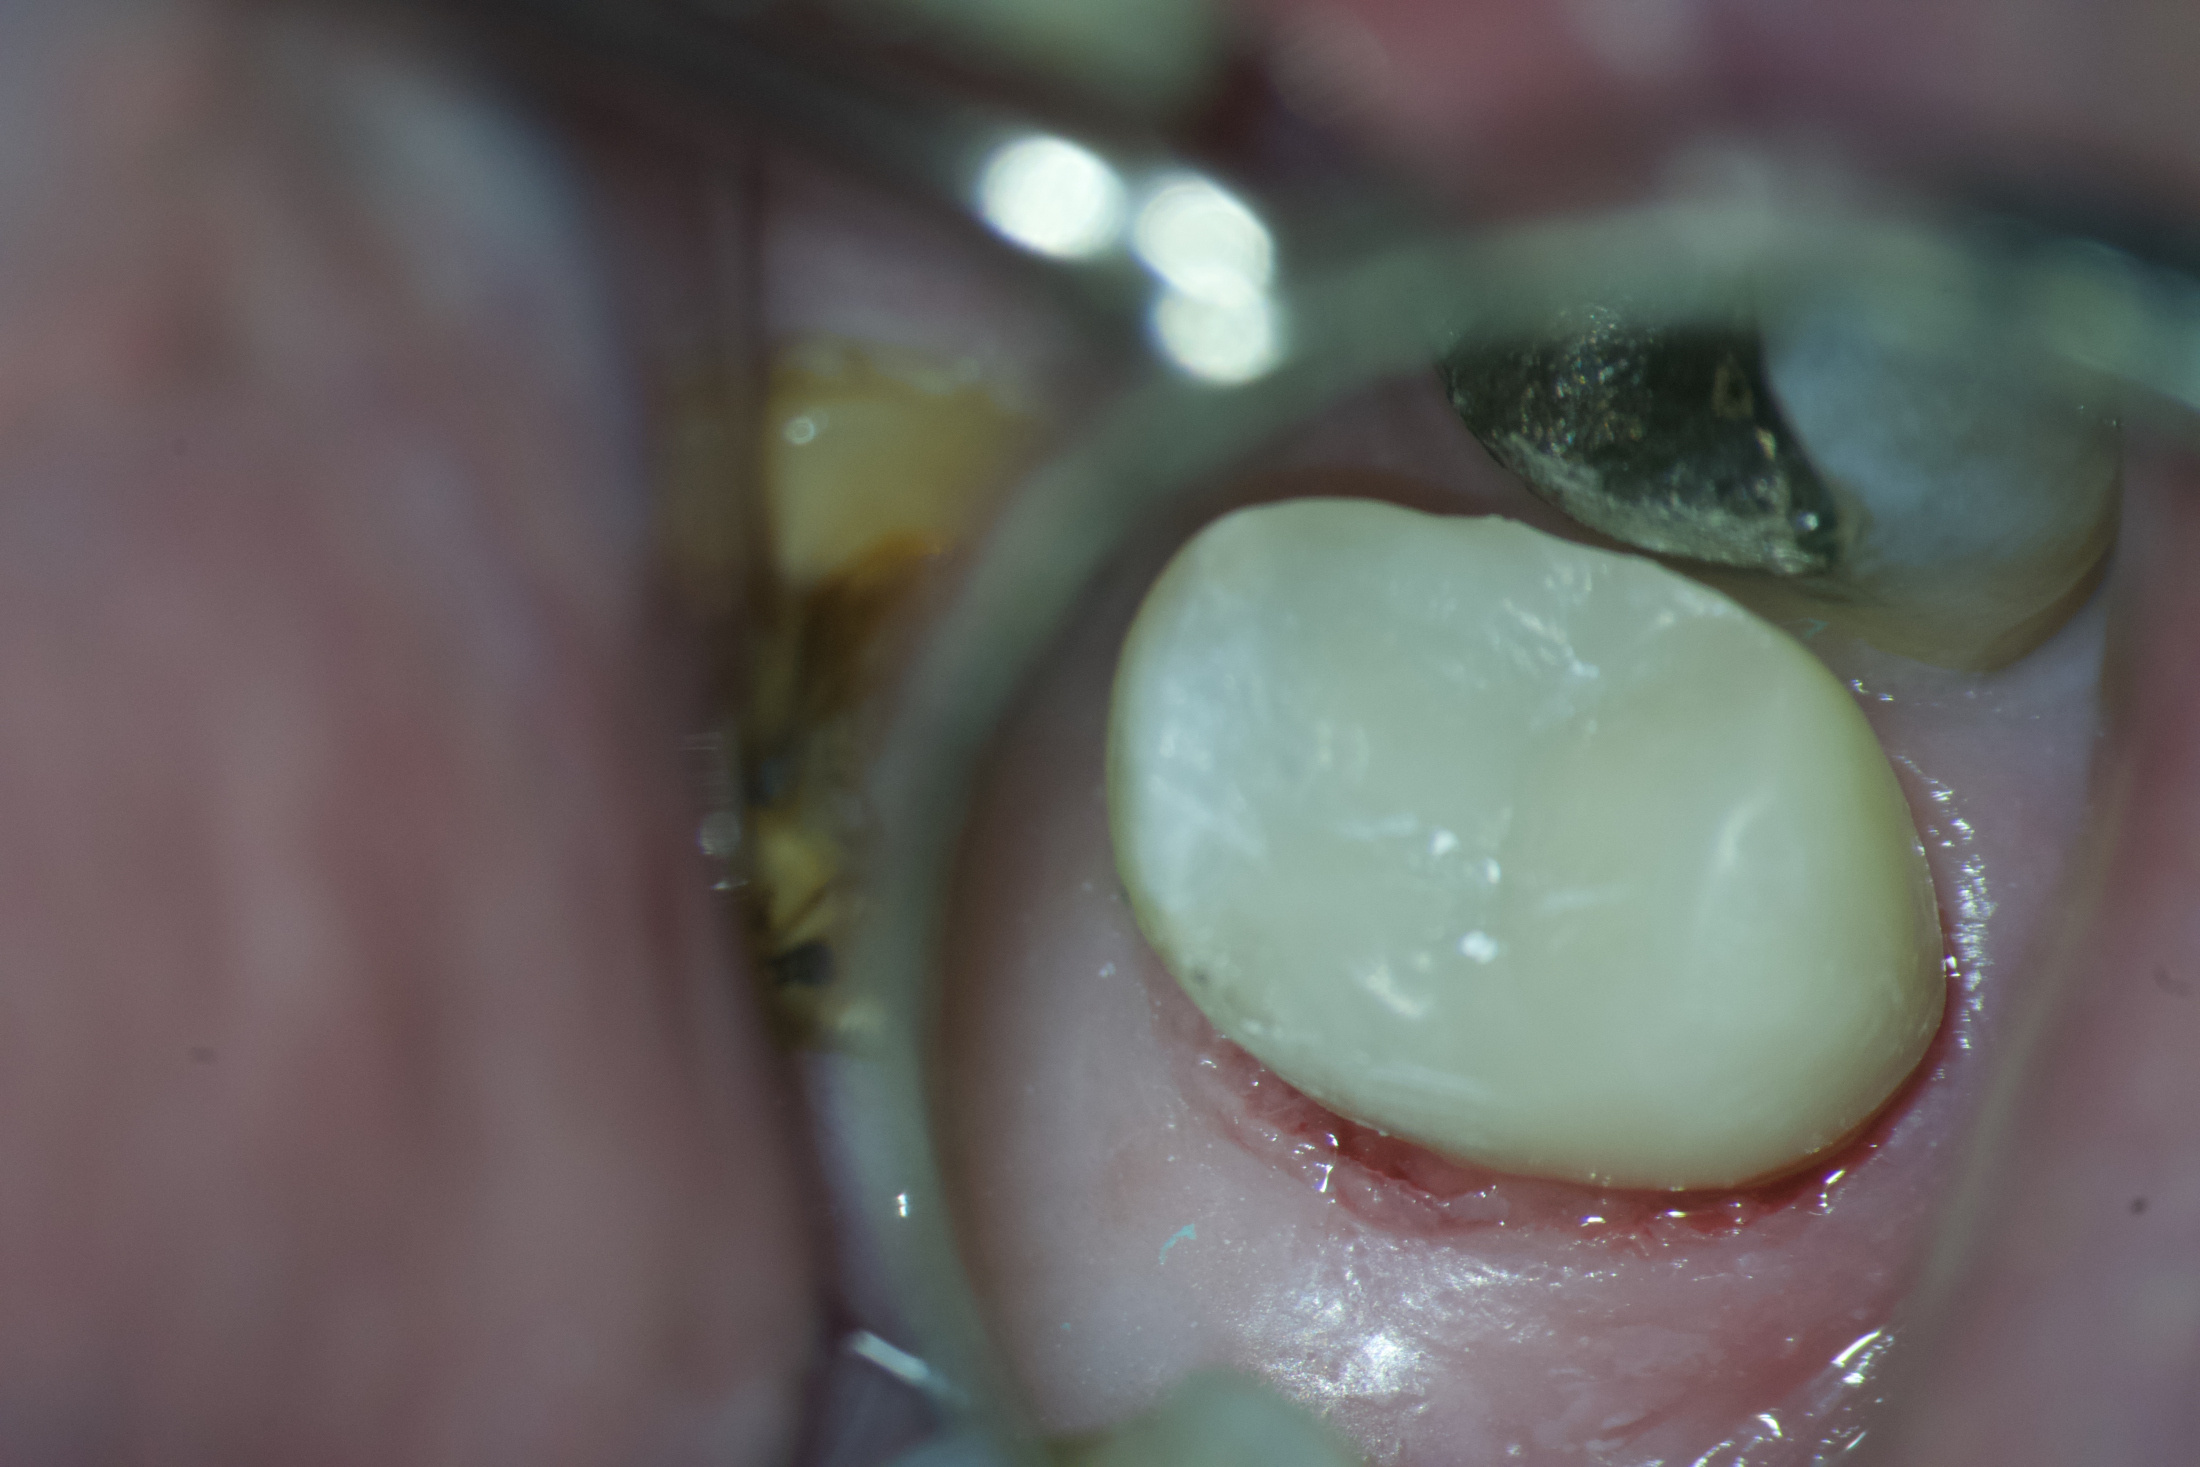

Remodelácia zlomeného zuba na počkanie